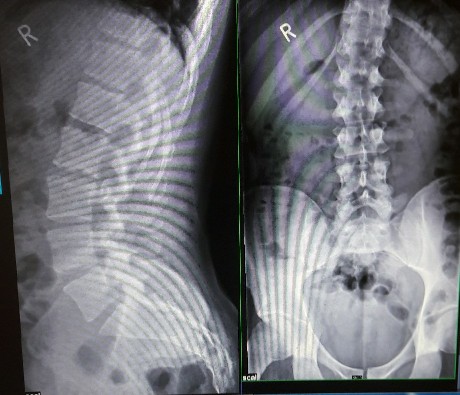

zunächst mal, ich habe Deine doppelt eingestellten gleichen Röntgenbilder (der unteren Wirbelsäule) gelöscht. Oder wolltest Du zwei unterschiedliche Röntgenbilder einstellen?

Entscheidend ist das Ergebnis und nach dem Foto und den Röntgenbildern zu urteilen, geht es hier um einen Rundrücken (Hyperkyphose), ein Hohlkreuz (Hyperlordose) sowie eine geringe begleitende Skoliose, was insbesondere bei einem Mann eine ganz typische Situation sein kann.

Insofern ist die Diagnose "leichter Scheuemann" keine vernünftige Diagnose! Anhand von Röntgenaufnahmen der gesamten Wirbelsäule sollten die entsprechenden Winkel ausgemessen werden.